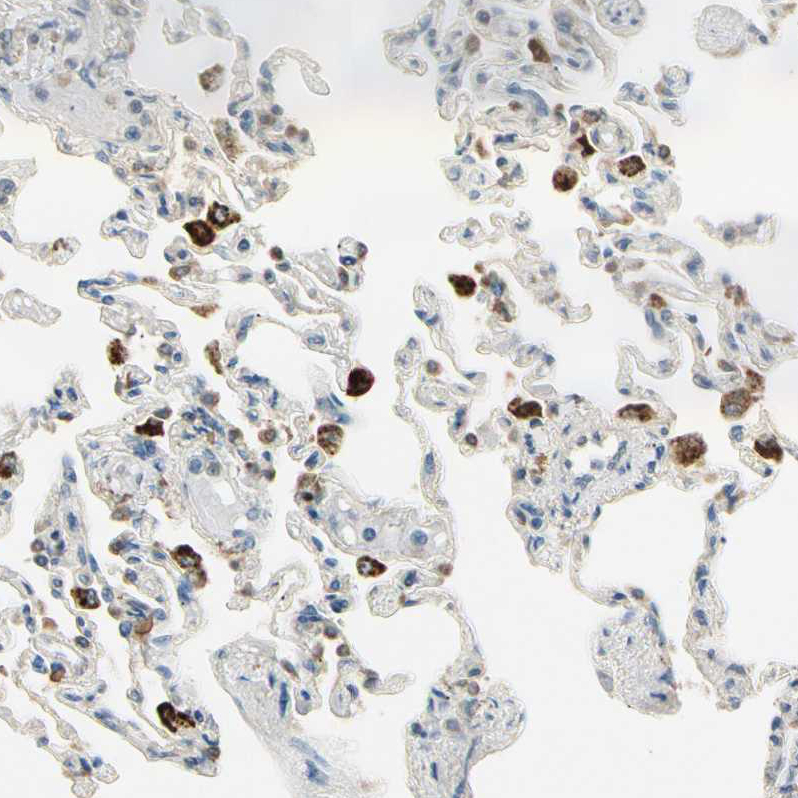

Immunohistochemical staining of human lung shows strong cytoplasmic positivity in macrophages.